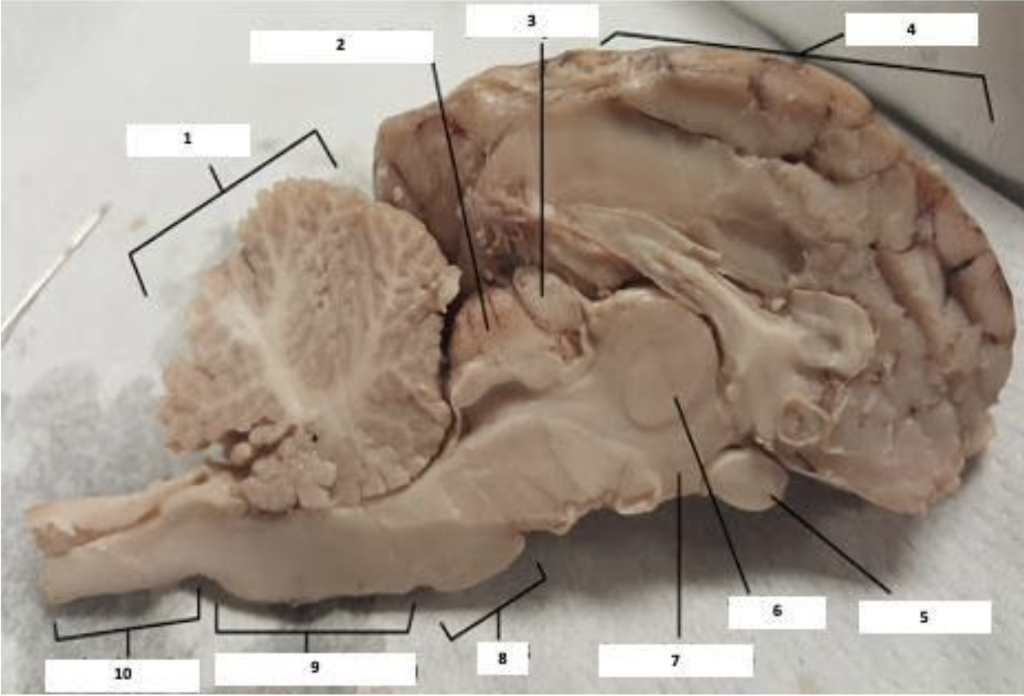

Cat Brain Anatomy Vet Verified Facts Common Disorders Catster hotsell, Brain structure of the cat Students Britannica Kids Homework Help hotsell, Removal and Study of the Cat Brain David Fankhauser hotsell, Feline Body Parts The Brain of a Cat Leisure Commando Arnold Plotnick hotsell, Gyri and sulci of the feline brain caudal view G. marginalis a g. Download Scientific Diagram hotsell, Dog Brain Anatomy Disease Seizures In Dogs Cats Safarivet hotsell, Gyri and sulci of the feline brain lateral view G. ectomarginalis. Download Scientific Diagram hotsell, Dog Brain Anatomy Disease Seizures In Dogs Cats Safarivet hotsell, 2 806 Animal Brain Anatomy Images Stock Photos 3D objects Vectors Shutterstock hotsell, Cat Brain vs Human Brain Differences Explained With Infographic Catster hotsell, Gyration of the Feline Brain Localization Terminology and Variability Pakozdy 2015 Anatomia Histologia Embryologia Wiley Online Library hotsell, Removal and Study of the Cat Brain David Fankhauser hotsell, Gyration of the Feline Brain Localization Terminology and Variability Pakozdy 2015 Anatomia Histologia Embryologia Wiley Online Library hotsell, Brain cortex ablated cat and its differences with other decerebrated. Download Scientific Diagram hotsell, 17.16 Brain Biology LibreTexts hotsell, Cat dissection lab labeled images PPT Free Download hotsell, Feline brain hi res stock photography and images Alamy hotsell, Cat Brain Anatomy Vet Verified Facts Common Disorders Catster hotsell, Solved Please help me label the median sagittal section Chegg hotsell, BRAIN ANATOMY AND FUNCTION SIVYER PSYCHOLOGY hotsell, High resolution MRI anatomy of the cat brain at 3 Tesla ScienceDirect hotsell, Is a cat brain like a human brain hotsell, THE BRAIN FROM TOP TO BOTTOM hotsell, The cat brain rendered 3 dimensionally. Caudal A dorsal B and. Download Scientific Diagram hotsell, Cat Brain Diagram Quizlet hotsell, Pin page hotsell, High resolution MRI anatomy of the cat brain at 3 Tesla ScienceDirect hotsell, Cat Brain by CellarDormouse on DeviantArt hotsell, CAT12 Manual hotsell, 770 Cat Brain Stock Illustrations Royalty Free Vector Graphics Clip Art iStock hotsell, Cat Brain Anatomy Vet Verified Facts Common Disorders Catster hotsell, Brain Definition Parts Functions Facts Britannica hotsell, Solved Please help me label this photo of the cat brain Chegg hotsell, 6 238 Cat Brain Royalty Free Photos and Stock Images Shutterstock hotsell, 105KB 2001 null null null 6 3 9 3 1 2003 null iANs5ZUjf7wPeM hotsell.